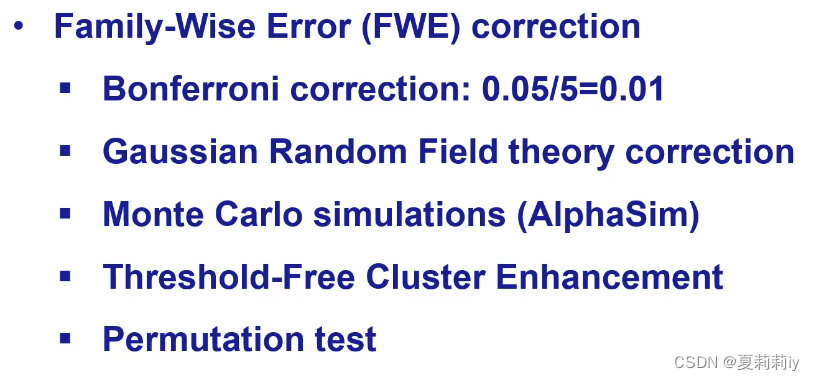

③Family-Wise Error(FWE):也有很多种办法,如下

④Gaussian Random Field Theory Correction(GRF Correction)

⑤AlphaSim Correction:不是很推荐

⑥Threshold-Free Cluster Enhancement(TFCE):